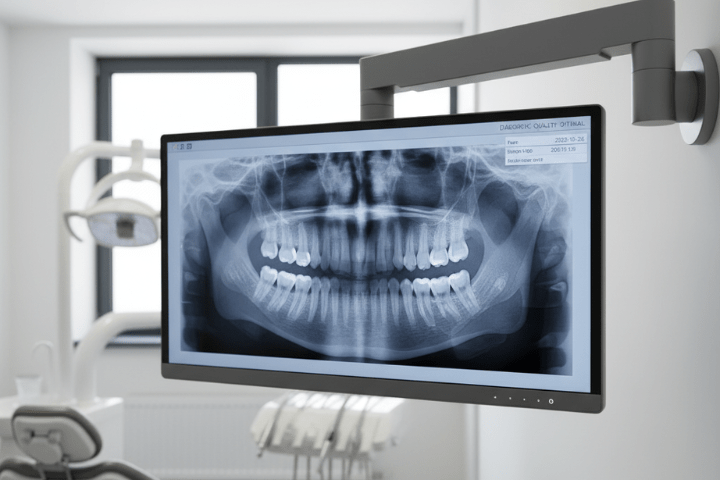

Bone/Gum Loss Treatment

Reconstructive Surgery for Bone and/or Gum Loss

When periodontal disease is more advanced, it can result in damaged gum tissue and/or bone loss, which then can lead to tooth loss. However, there are surgical solutions that can be used to restore the tissue and/or the bone before tooth loss occurs.